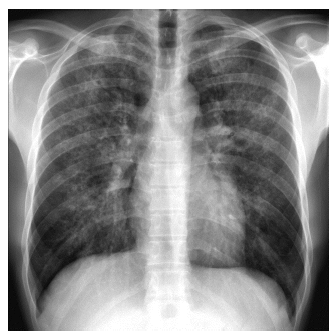

7,47, pCO2 30 HCO3 17, pO2 64. Radiografia

simples de tórax mostra padrão de

opacificação intersticial de predomínio perihilar e pequenas pneumatoceles, sem

derrame pleural, conforme a imagem a

seguir: